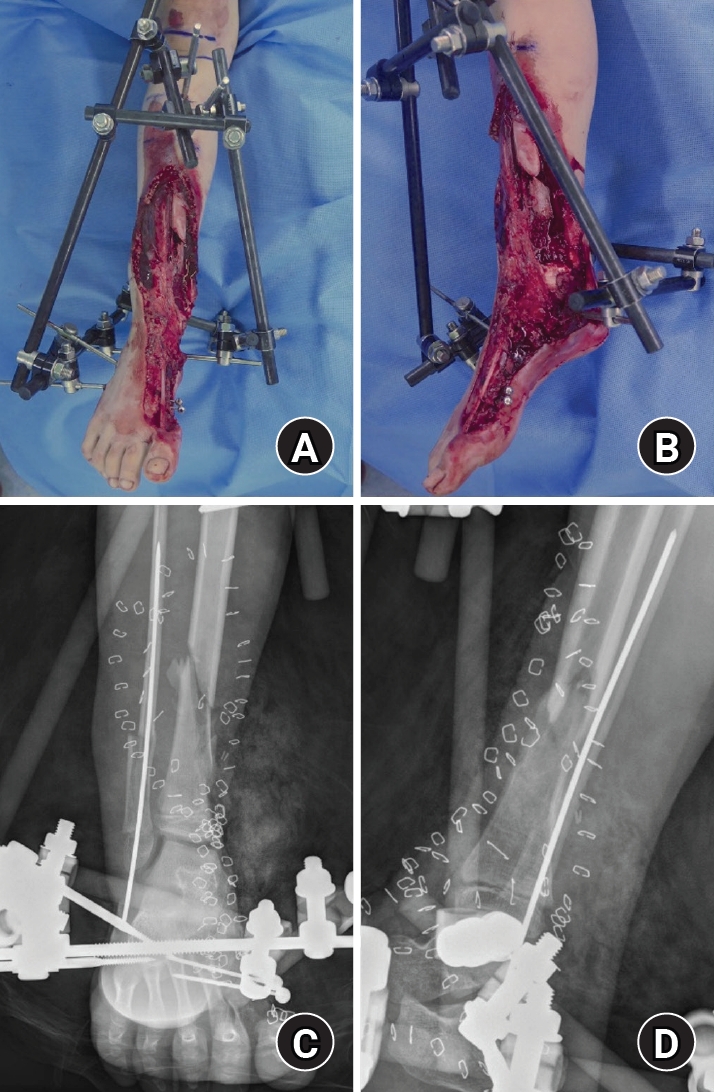

At presentation, extensive soft-tissue loss of the medial ankle/foot was noted, consistent with a high-energy crush/degloving mechanism (Fig. 1). The wound severity raised concerns for soft-tissue viability, contamination, and subsequent infection risk, and suggested the need for a staged approach with temporary stabilization followed by definitive reconstruction.

Initial plain radiographs demonstrated a distal tibiofibular fracture in a skeletally immature patient, with associated medial-sided midfoot injuries (first metatarsal, medial cuneiform, and medial navicular bone defects) (Fig. 1). During staged management, traumatic loss of the distal tibial medial malleolus was identified, consistent with a Salter-Harris type VI injury pattern and raising concern for physeal bar formation and medial ankle instability due to deltoid ligament deficiency [2,3]. The medial malleolar bony defect was measured intraoperatively as 2.5×2.0 cm to guide graft contouring. Given the severity of the soft-tissue injury, a staged strategy was adopted [1,4].

Fig. 1.

Initial injury on June 14, 2016. (A) Anteroposterior gross photograph obtained at presentation showing a severe crush and degloving injury involving the medial aspect of the right ankle and foot. (B) Lateral gross photograph obtained at presentation demonstrating extensive soft-tissue loss and degloving injury of the medial right ankle and foot. (C) Anteroposterior radiograph obtained at presentation showing an associated distal tibiofibular fracture in a skeletally immature patient. (D) Lateral radiograph obtained at presentation demonstrating the distal tibiofibular fracture.

Fig. 1. Initial injury on June 14, 2016. (A) Anteroposterior gross photograph obtained at presentation showing a severe crush and degloving injury involving the medial aspect of the right ankle and foot. (B) Lateral gross photograph obtained at presentation demonstrating extensive soft-tissue loss and degloving injury of the medial right ankle and foot. (C) Anteroposterior radiograph obtained at presentation showing an associated distal tibiofibular fracture in a skeletally immature patient. (D) Lateral radiograph obtained at presentation demonstrating the distal tibiofibular fracture.